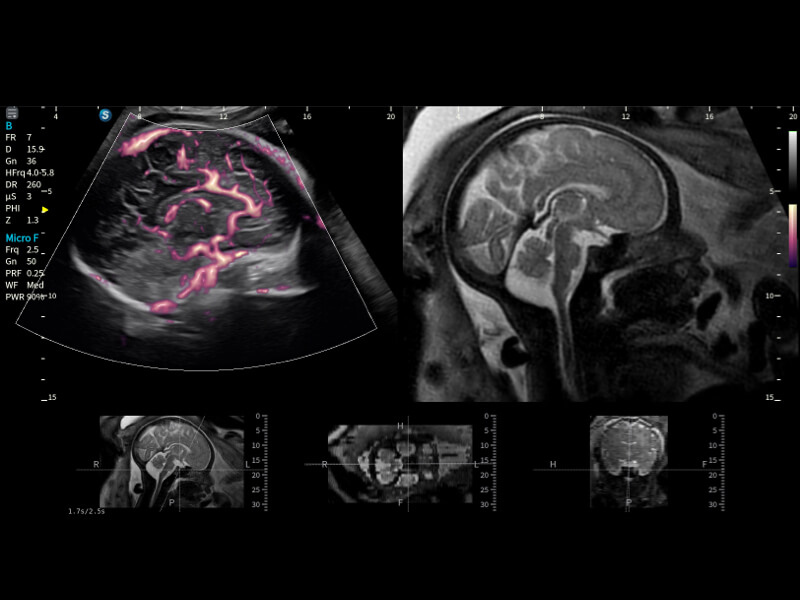

作为开立医疗全新打造的超高端旗舰超声产品,从探头抬起唤醒开启扫查到多维探头发射接收,通过先进的场成像发射、自适应聚合重建等技术,基于RF Data原始射频数据在图像生成、高端功能等方面实现突破,为妇产科、儿科提供全方位临床解决方案。

梦溪®P80以“关爱女性”为基石,提供全方位的解决方案,量身定制以满足女性的健康需求,涵盖妇科、生殖健康检查、产前筛查及产后康复等领域。